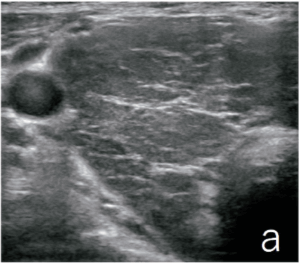

甲状腺右葉の超音波 B モード像(a)及びパワードプラ像(b)(別冊No. 5)を別に示す。最も考えられるのはどれか。

No. 5